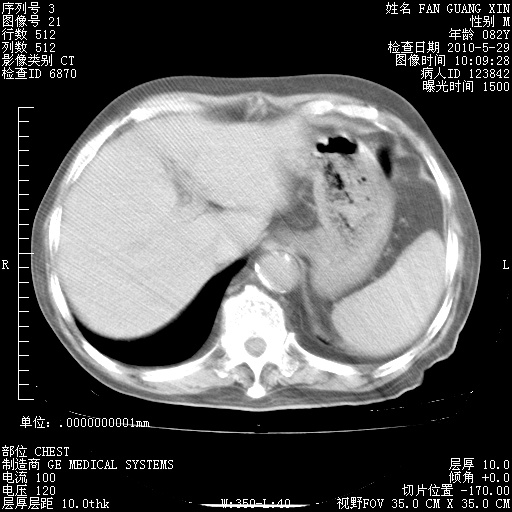

再治疗10天后的肺部CT 纵膈窗

从白细胞总数和中性比例看好像合并感染。肺部纹理好像比上次多,支气管炎?其他感染?

阅读此次胸部CT,肺间质渗出性改变较入院时有吸收。目前从体温、白细胞、中性分叶明显增高,肯定存在细菌感染(发生医院感染哦,若无消化道及泌尿系统等感染的依据,肺部感染可能大)。若你院头孢哌酮舒巴坦钠耐药率较高,同意你的方案,若48小时体温仍高,可考虑使用碳青霉稀类抗菌药物,同时可予超声雾化、注意滴数时加大液体量。白蛋白33.30g/L较低哦,需加强营养等支持治疗。